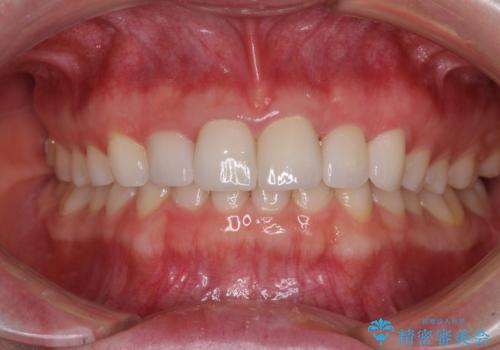

前歯のブリッジが気に入らない 歯肉移植術を併用した前歯のブリッジ

- 接着タイプの前歯のブリッジが不自然であるとのことで来院された患者様です。

事前に装着されていた接着タイプのブリッジは、歯の切削量が少ない反面、接着界面から虫歯が進行しやすく、脱落リスクが高くなるというデメリットがあります。